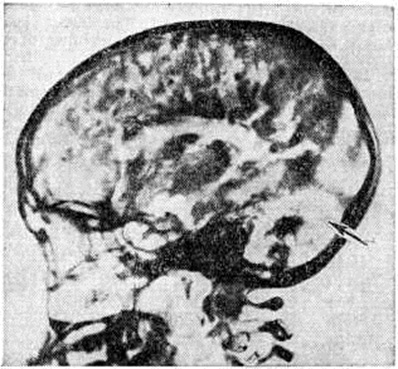

Характерными патоморфологическими признаками Оливопонтоцеребеллярная атрофия являются: асимметричная атрофия белого вещества мозжечка (рисунок 1), выраженная в большей степени в полушариях, чем в черве, при сохранности ядерных образований мозжечка; сморщивание и глиоз ядер моста (рисунок 2) и дегенерация средней ножки мозжечка; сморщивание и глиоз олив (рисунок 3), утрата наружных дугообразных волокон в мозжечке и дегенерация нижней ножки мозжечка; вторичная утрата грушевидных нейроцитов (клеток Пуркинье), главным образом из внутреннего гранулярного слоя коры мозжечка; полная сохранность верхней ножки и клочка мозжечка, а также узелка червя. В большинстве случаев патологический изменения диффузны. Могут поражаться также чёрная субстанция и базальные ядра, проводящие пути и задние корешки спинного мозга, грудные столбы (нейроны передних и задних столбов Кларка), лобные и височные отделы коры больших полушарий мозга, ядра III, VII, IX, X и XI пар черепных нервов. При гистологический исследовании в поражённых отделах мозга определяются демиелинизация нервных волокон, дегенеративные изменения нейронов и разрастание нейроглии. Клиническая картина. Первым симптомом спорадической формы Оливопонтоцеребеллярная атрофия является атактическая походка (смотри полный свод знаний Атаксия), чаще появляющаяся в возрасте 35—40 лет, однако она может встречаться и у детей. Затем появляется дизартрия (смотри полный свод знаний), атаксия рук, интенционный тремор и дрожание головы (смотри полный свод знаний Дрожание), иногда наблюдается повышение сухожильных рефлексов (смотри полный свод знаний), патологический пирамидные знаки. Часто у больных отмечается также недержание мочи, а на более поздних стадиях заболевания психические нарушения в виде депрессии или деменции, паркинсоноподобный синдром (смотри полный свод знаний Паркинсонизм), гиперкинезы (смотри полный свод знаний), снижение остроты зрения вследствие пигментного ретинита (смотри полный свод знаний Тапеторетиналъные дистрофии), офтальмоплегия (смотри полный свод знаний), парез мимической мускулатуры, бульбарные нарушения (смотри полный свод знаний Бульбарные рефлексы), снижение или отсутствие сухожильных рефлексов.

Диагноз устанавливают с помощью пневмоэнцефалографического исследования (смотри полный свод знаний Пневмоэнцефалография), при котором отмечается повышенное скопление воздуха в задней черепной ямке (рисунок 4); менее постоянно расширение боковых желудочков, особенно их передних рогов, и скопление воздуха на месте атрофированных лобных долей. В целях диагностики может быть использована и компьютерная томография головы, которая при Оливопонтоцеребеллярная атрофия выявляет атрофию мозжечка, расширение околомостовой цистерны и иногда гидроцефалию.